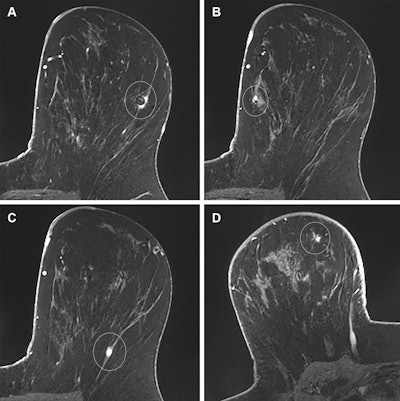

Images in a 39-year-old woman with a remote history of right breast cancer and a new diagnosis of multicentric left breast cancer; this case illustrates appropriate auditing of true- and false-positive results. (A) Axial T1-weighted postcontrast image from preoperative breast MRI shows a small invasive mammary carcinoma with biopsy clip susceptibility artifact (circle) in the lateral left breast that was diagnosed before MRI. (B) Axial T1-weighted postcontrast image from the same examination reveals a smaller invasive mammary carcinoma with biopsy clip susceptibility artifact (circle) in the medial left breast that was also diagnosed before MRI. For the purpose of auditing in this study, the larger of these two malignancies was considered the index malignancy. (C) Axial T1-weighted postcontrast image from the same examination demonstrates an additional small mass in the posterior aspect of the left breast (circle). It was described as suspicious, and a third focus of invasive mammary carcinoma was diagnosed at MRI-guided biopsy. This pathologic result was audited as a true-positive ipsilateral finding. (D) Axial T1-weighted postcontrast image from the same examination shows a fourth mass in the contralateral right breast (circle), which was also described as suspicious. MRI-guided biopsy yielded benign fat necrosis and stromal fibrosis, which was audited as a false-positive contralateral finding.RSNA

The study included 1,533 preoperative MRI exams with a median patient age of 55. Of the total exams, 464 showed 609 suspicious breast imaging findings. Image-guided biopsy that followed for 432 of these findings revealed 139 malignancies.

The overall abnormal interpretation rate was 30.3%, PPV2 was 22.8%, PPV3 was 32.2%, and the additional cancer detection rate was 90.7 per 1,000 exams.